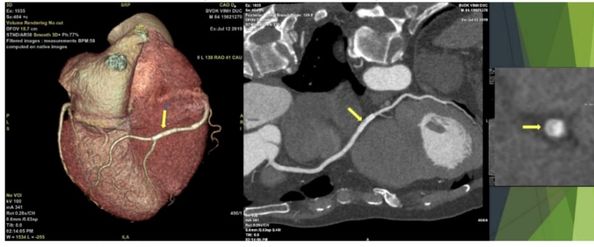

Cắt lớp vi tính động mạch vành là một kỹ thuật thu hình tim – động mạch vành 3 chiều (3D) bằng cách sử dụng máy cắt lớp vi tính thế hệ mới, cho ra hình ảnh rõ nét và chính xác, giúp chẩn đoán bệnh lý tim – động mạch vành.

Độ chính xác >90% ở hầu hết các nghiên cứu lớn trên thế giới và sử dụng hệ thống tiên tiến tương tự tại bệnh viện chúng tôi.